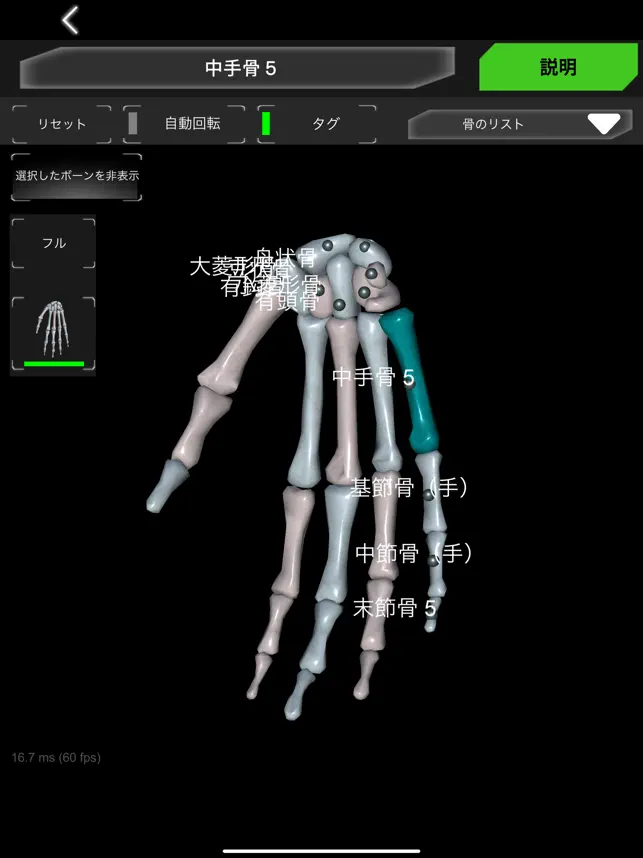

人間の骨格の解剖学に関する情報を 3 次元モデルで示します。

骨システムの 3 次元モデルとそれらすべての説明が表示されます。

頭蓋骨、背骨、肋骨、胸骨、大腿骨、脛骨、腓骨などの各骨を触るとその情報が表示されます。